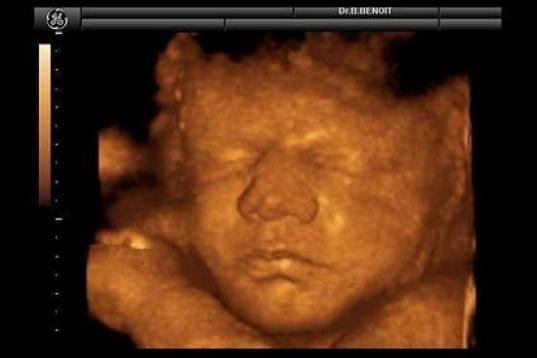

En esta galería puedes ver en fotos como es el desarrollo de un feto de semana en semana:

Desarrollo del feto, en fotos

Ver la galería